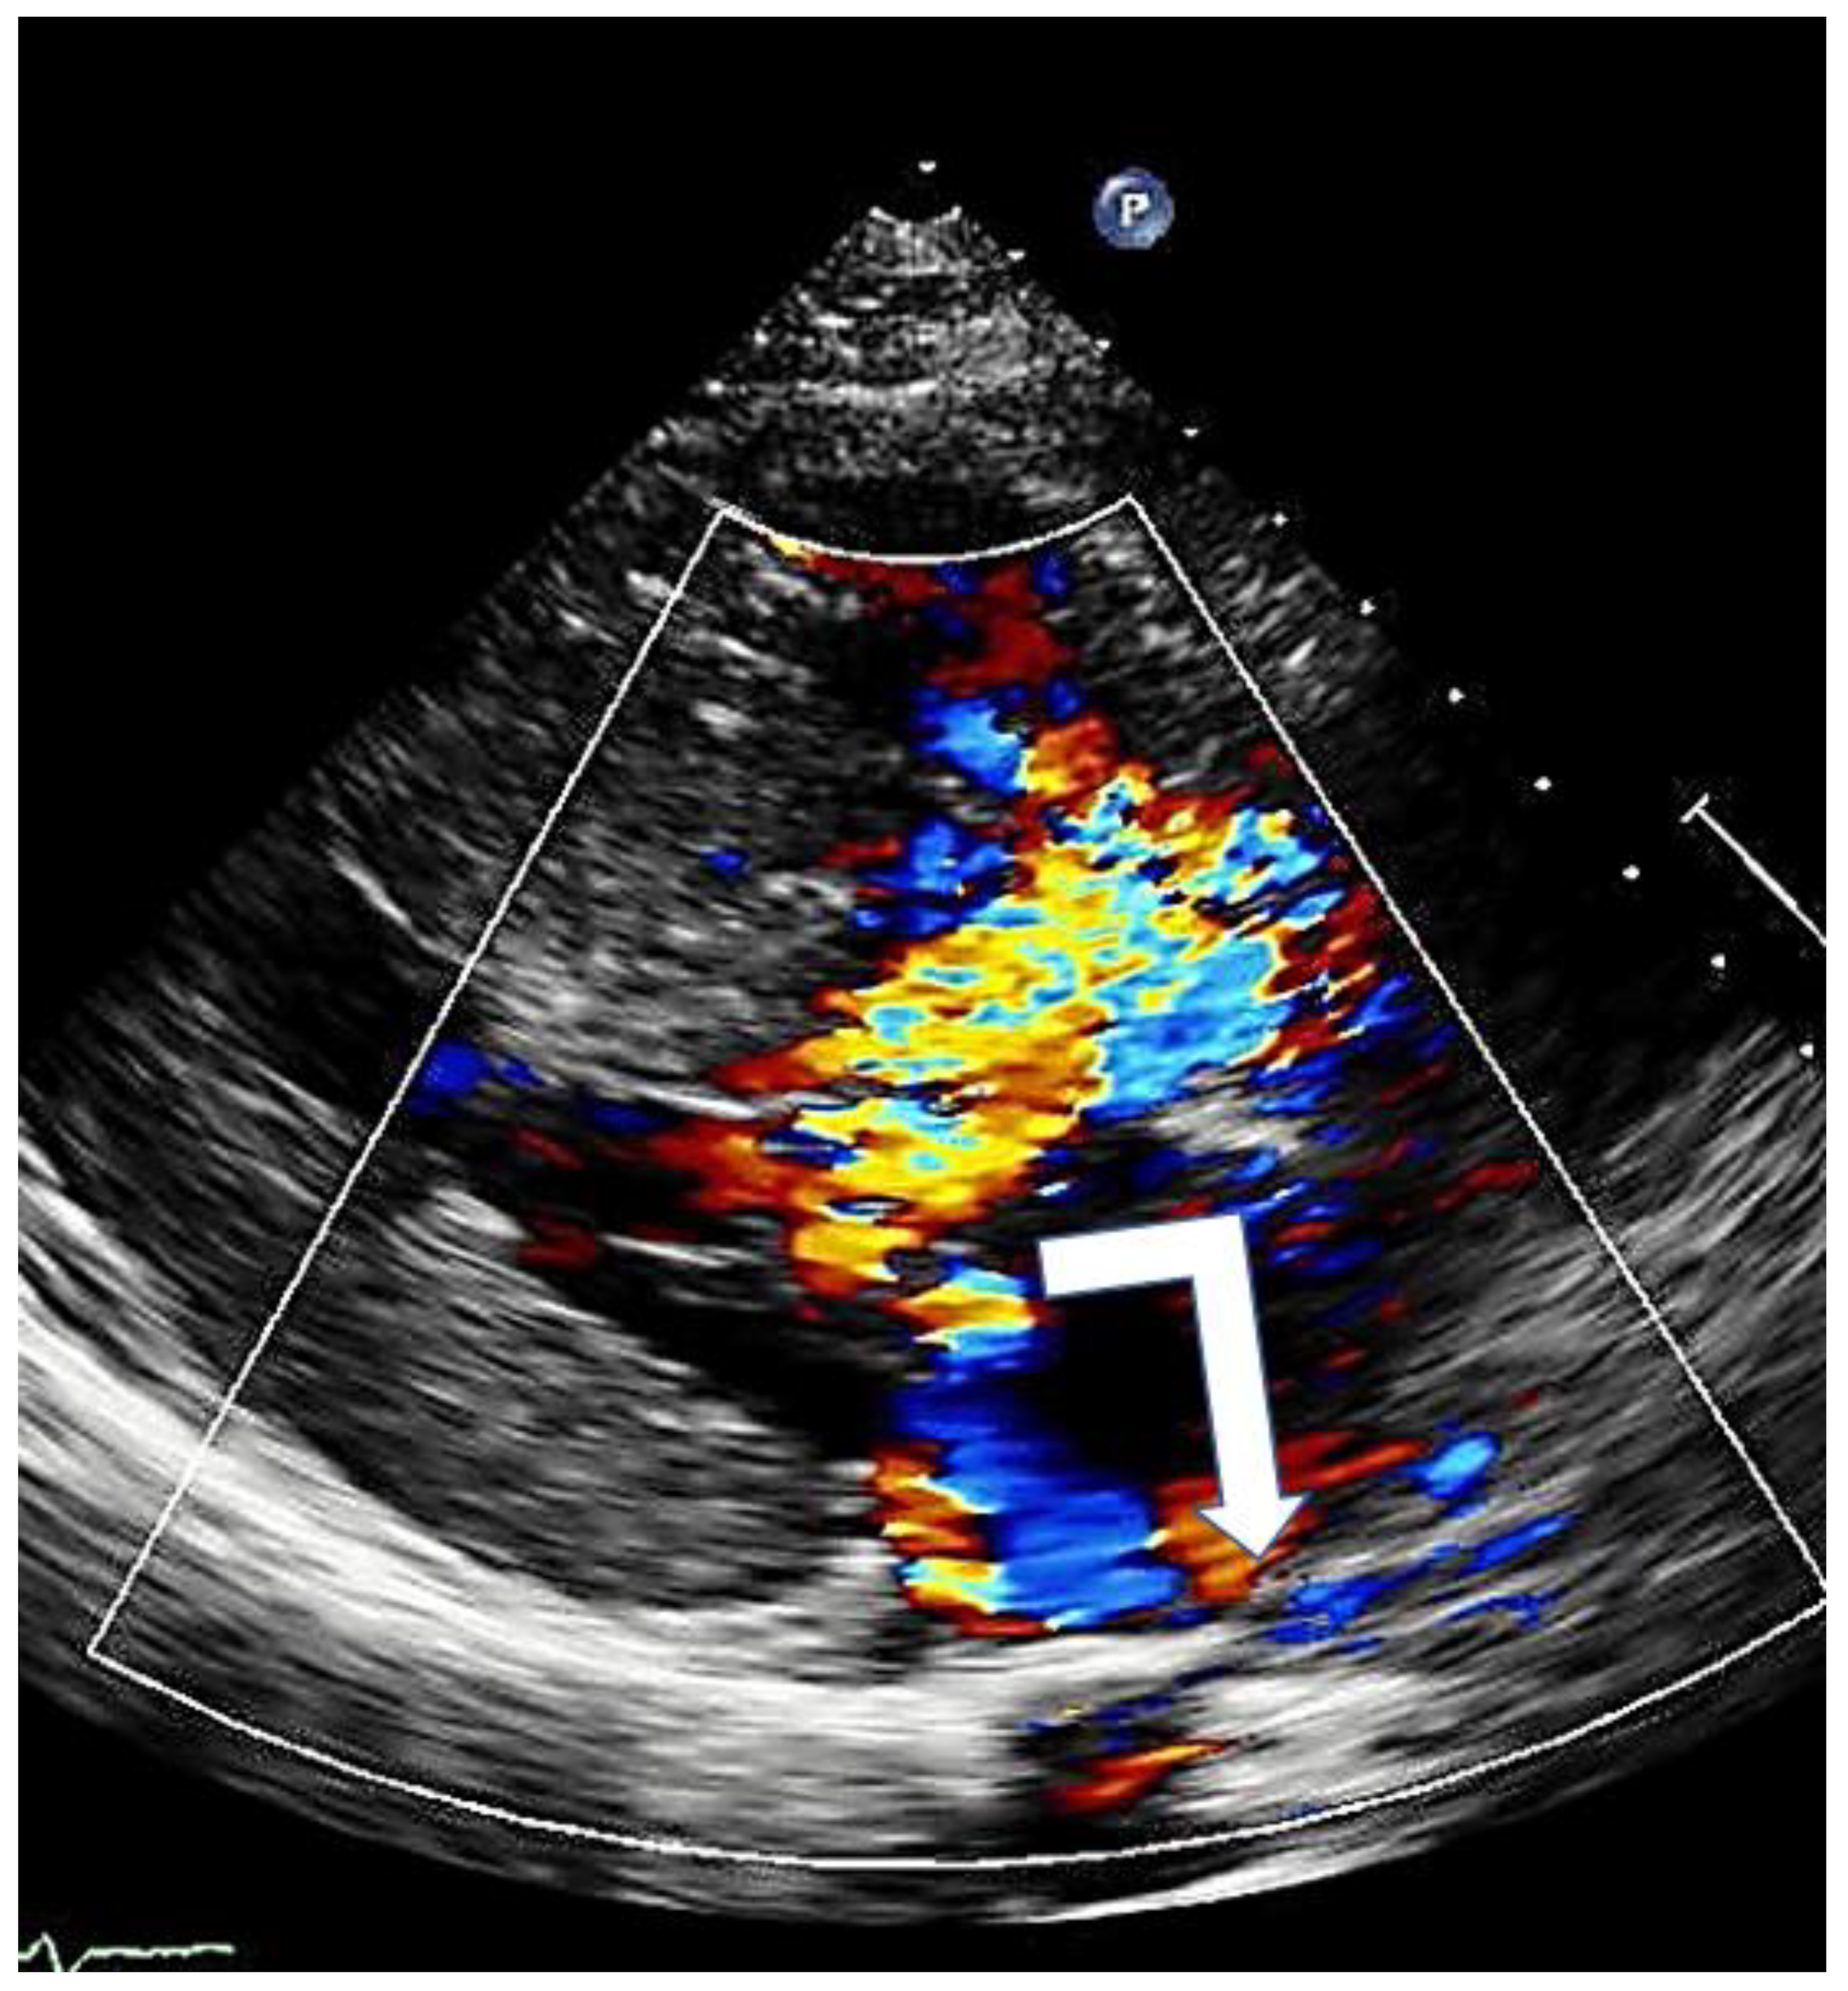

Figure 6. Mitral regurgitation in hypertrophic cardiomyopathy due to systolic anterior motion of the mitral valve; typical eccentric posterior direction (arrow).

Mitral regurgitation (MR), caused by SAM, is observed in almost all patients with HOCM anterior mitral leaflet elongation and the associated increased mobility impairs adequate leaflet coaptation, resulting in SAM-related, eccentric posterior and lateral MR (Figure 6). When additional mitral valve abnormalities other than SAM are not observed, a direct relation between the pressure gradient and the severity of MR is evident. A central or anterior jet often indicates the presence of organic mitral valve disease [17].